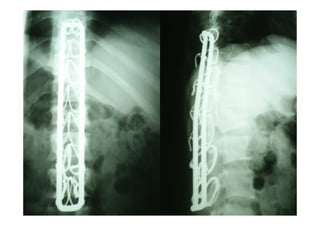

figura